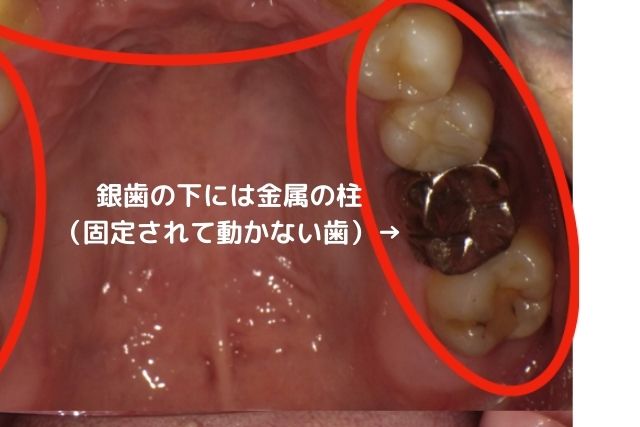

②銀歯を被せた歯がまた虫歯を再発する

銀歯と歯は歯科用の接着材でペタンとくっつけています。

しかし、正確にいうとぴったりとくっついているわけではありません。

封鎖性が非常に弱いため隙間があるのです。

銀歯を入れる際に歯との隙間を接着材で埋め、

くっつけているだけ、です。

隙間があるので隙間からは細菌は侵入し放題です。

お口の中には目に見えない何百億の細菌が存在します。

侵入し放題の虫歯菌により、せっかく治療した歯の中に虫歯が再発します。

銀歯のセメントも劣化してくるので、古い銀歯の中で、元々の歯が真っ黒になっていたといったこともよくあります。